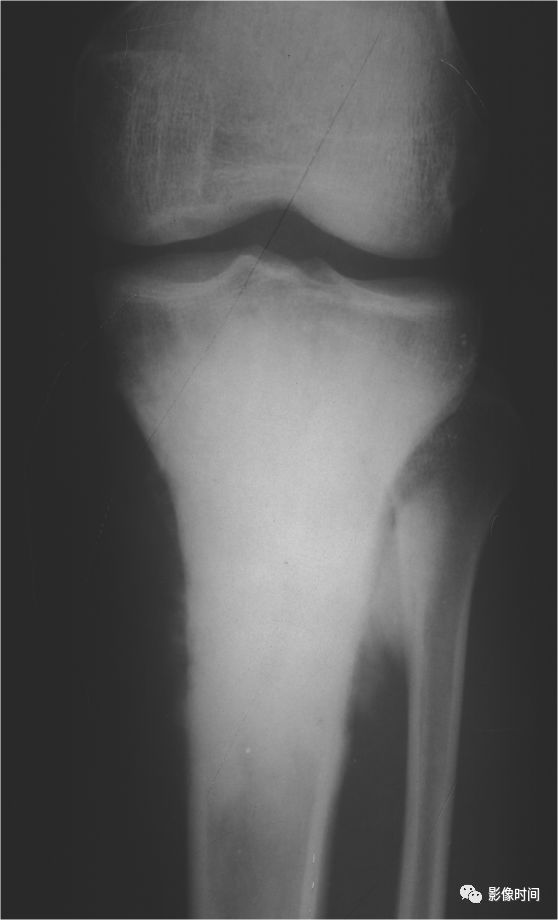

肿瘤对骨骺板和关节软骨的破坏是对骨破坏的继续。缺乏血管的骨骺板对恶性肿瘤有抵抗作用,骨骺板可暂时阻止肿瘤的蔓延,但当肿瘤进一步发展时, 骨骺板亦可被破坏,X 线平片或 CT 可表现为先期钙化带密度减低、中断或消失。MRI 可显示肿瘤从干骺端跨越骨骺板侵犯骨骺(图 15、图 16)。

肿瘤突破关节软骨向关节腔发展时, 可表现为关节面破坏、塌陷(图 17), 关节腔内出现软组织肿块。少数良性骨肿瘤如软骨母细胞瘤, 亦可超越骺板向两侧发展或突入关节腔内, 此为肿瘤膨胀生长所致, 而非浸润性破坏。

图 15 骨骺板破坏:骨肉瘤

图 16 骨骺板破坏:骨肉瘤

图 17 关节软骨破坏:骨肉瘤